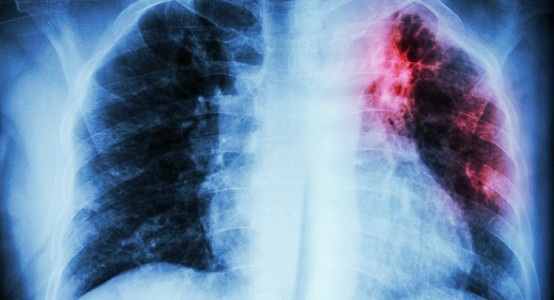

В Узбекистане обсуждают расширение применения науки и технологий в решении проблемы туберкулеза